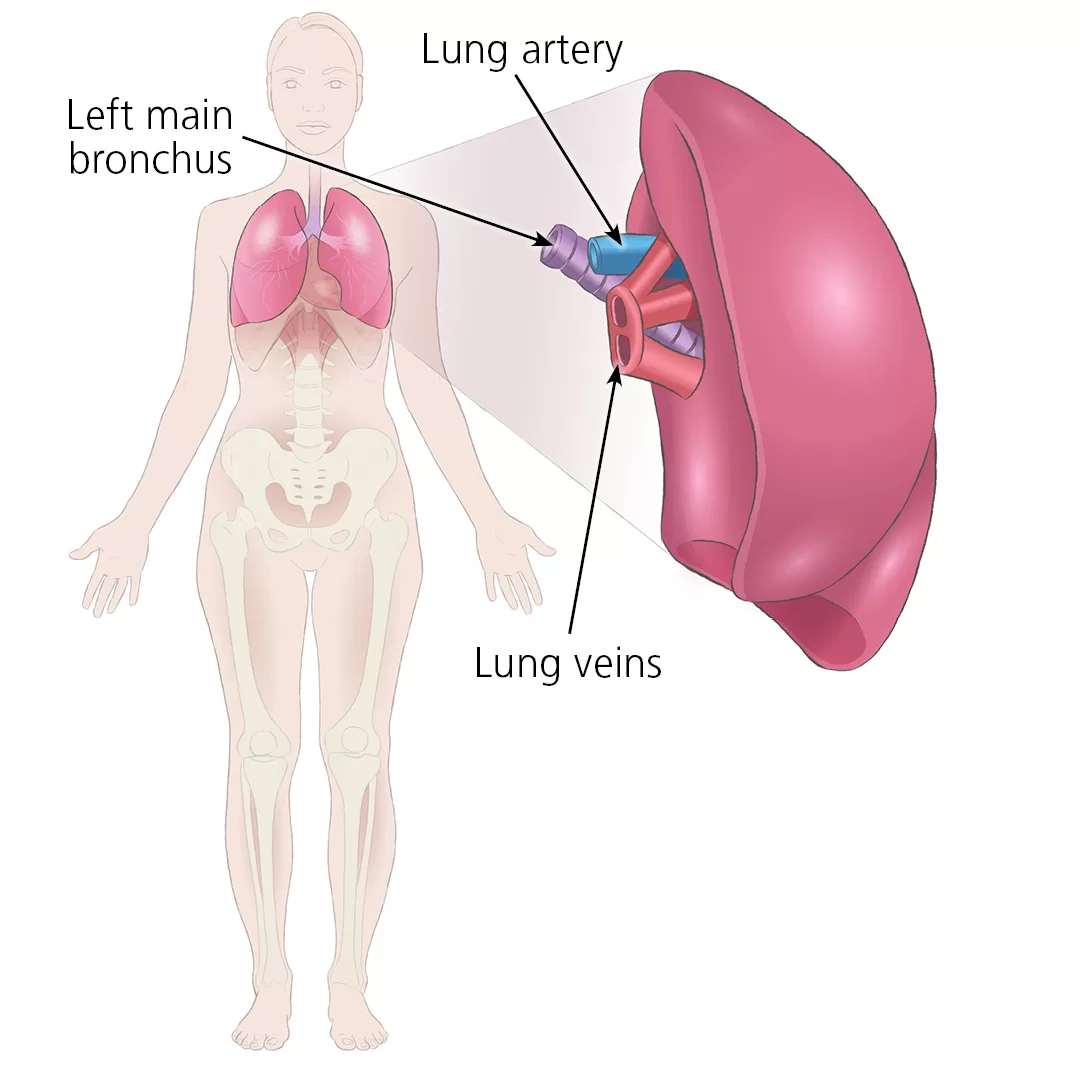

5. Bronkus (Cabang Tenggorokan)

Bronkus atau cabang tenggorokan merupakan saluran penghubung antara rongga hidung, rongga mulut dan paru-paru. Dinding batang tenggorokan (Trakea) tersusun dari cincing-cincin tulang rawan yang di dalamnya terdapat rambut-rambut getar (silia) yang berfungsi menyaring udara pernapasan.

Trakea bercabang menjadi dua bagian yaitu bronkus kanan dan bronkus kiri. Struktur lapisan mukosa bronkus sama dengan trakea, hanya tulang rawan bronkus bentuknya tidak teratur dan pada bagian bronkus yang lebih besar cincin tulang rawannya melingkari lumen dengan sempurna. Bronkus bercabang-cabang lagi menjadi bronkiolus.

7. Paru-Paru (Pulmo)

Paru-paru terletak di rongga dada tepat di atas sekiat diafragma. Diafragma adalah sekat rongga badan yang membatasi rongga dada dan rongga perut. Paru-paru terdiri dari dua bagian.

Paru-paru kanan memiliki tiga lobus, sehingga lebih besar dari paru-paru kiri yang terdiri dari dua lobus. Paru-paru dibungkus oleh dua lapis selaput paru-paru atau pleura. Di bagian dalam paru-paru terdapat gelembung halus yang merupakan perluasan permukaan paru-paru yang disebut alveolus, dan jumlahnya ± 300 juta buah. Luas permukaan alveolus diperkirakan mencapai 160 m² atau 100 kali lebih luas daripada luas permukaan tubuh.